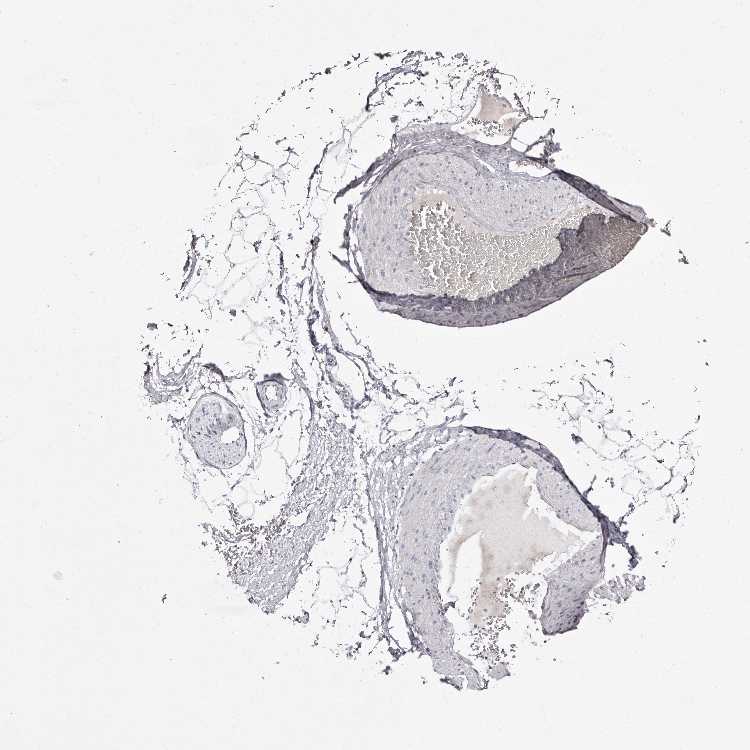

SOFT TISSUE 1 - Antibody stainingi

Antibody staining in the annotated cell types in the current human tissue is reported as not detected, low, medium, or high, based on conventional immunohistochemistry profiling in selected tissues. This score is based on the combination of the staining intensity and fraction of stained cells.

Each image is clickable and will lead to virtual microscopy that enables deeper exploration of all samples and also displays staining intensity scores, fraction scores and subcellular localization as well as patient and tissue information for each sample.

Antibody HPA009128Antibody HPA029564

Chondrocytes Medium-

Fibroblasts LowNot detected

Peripheral nerve Not detectedNot detected

SOFT TISSUE 2 - Antibody stainingi

Chondrocytes -Not detected

Fibroblasts MediumNot detected

Peripheral nerve Low-